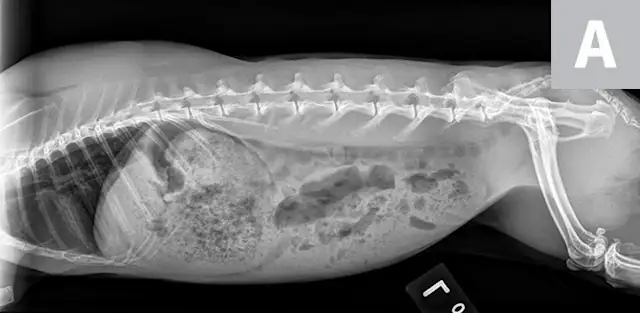

Victor was sedated with midazolam (0.5 mg/kg IM) to reduce stress during IV catheter placement and diagnostic testing. Abdominal radiographs (Figure 2) showed heterogeneous material in the stomach, which was inappropriately large for an anorexic rabbit; no obstructive pattern was seen.

FIGURE 2A

Abdominal and partial thoracic radiograph, left lateral view (A); abdominal and partial thoracic radiograph, right lateral view (B); and abdominal and thoracic radiograph, ventrodorsal view (C) showing heterogeneous material in the stomach but no obstructive pattern